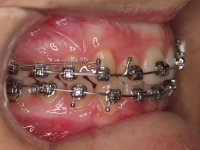

Clase II paciente 15 años

La paciente O.O. acude a nuestra consulta por:

– Canino 13 e incisivo lateral 42 en posición ectópica.

– Canino 23 incluido.

Con lo que decide realizarse un tratamiento de ortodoncia de duración de 24 meses con brackets damon Q.

CASO COMPLETO: